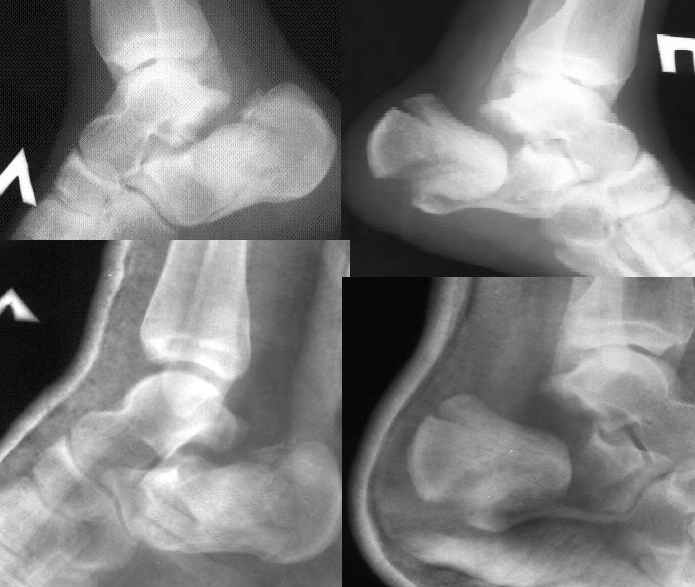

Спасибо! Но... В данном случае имеет место значительная компрессия тела пяточой кости (с обеих сторон, разумеется). Я мыслю, что необходима костная пластика. И ещё, - напрочь отсутствуют пластины для остеосинтеза пяточных костей. Возможно ли применить обычные реконструктивные пластины, или, на худой конец, спицы?

К сожалению невозможно применить пластину реконструктивную она применяется только когда пяточная кость состоит из двух половин.Пластины есть у всех даже российских производителей стоимостью от 2 тыс.рублей и до 25 тыс.Если ничего не найдёте всё равно открытая репозиция костная пластика обязательно и спицы снизу вверх в таранную кость.Желаю удачи.С уважением Дрягин.Просто думаю будет обидно если получится хорошая репозиция а пластины не окажется.И ещё в один день две пятки не берите может не хватить сил.Поначалу часа 4 пока разберётесь что и откуда.

Справа ситуация сложнее так как имеется помимо перелома имеется вывих тела пяточной костиПоэтому даже если удастся достигнуть хорошей репозиции необходимо сделать первичный подтаранный артродез.Иначе кость не будет держать в своём ложе.Но пластина нужна обязательно чтобы восстановить форму пятки.С уважением Дрягин

Если нет опыта применения в подобных случаях накостного остеосинтеза, весьма велик риск осложнений: в первую очередь нероза кожи в обл. операционной раны со всеми вытекающими. Альтернативой может служить чрескостный остеосинтез.